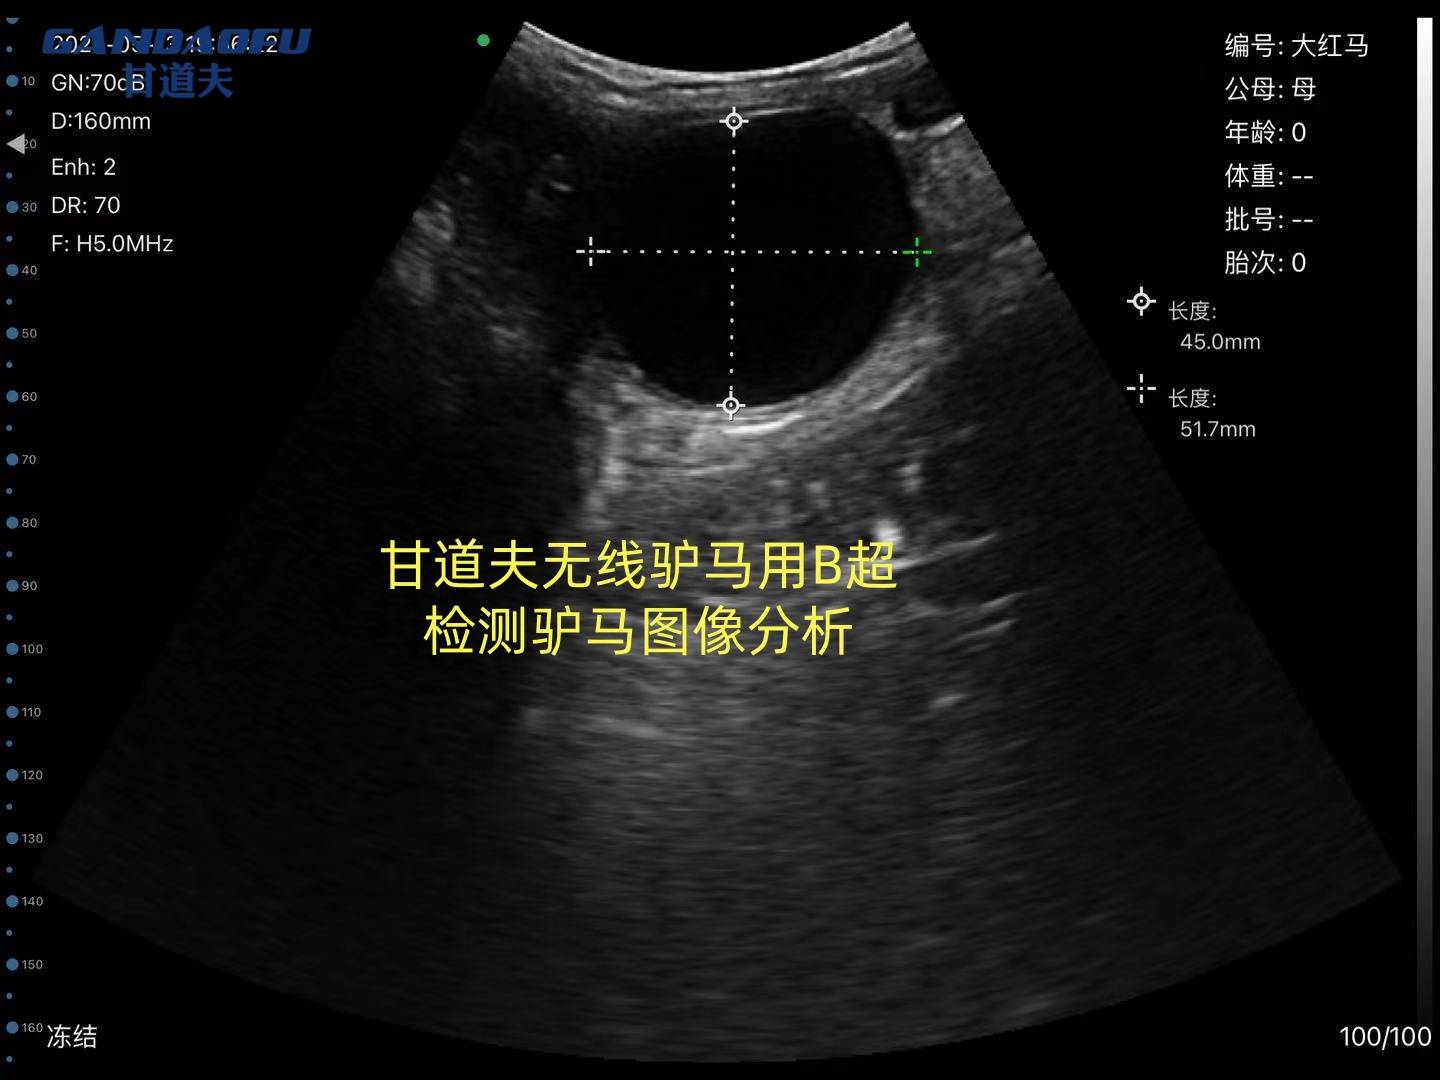

马用B超直肠检测母马怀孕在母马配种后早14天可见孕囊("向日葵征")胎心监测:25天左右可检测到心跳(120-160次/分)注意:驴怀骡时可能出现假阴性孕酮检测:维持在>4ng/ml水平 中期诊断(30-180天)30天:子宫角不对称,孕角增大 60天:孕角如排球大小 90天:可触及胎儿浮动感,外阴观察妊娠3个月后:阴唇闭合呈"菊花纹"皱褶阴道检查:宫颈粘液栓形成晚期诊断(180天至分娩),腹围测量法妊娠8个月:腹围增加15-20cm胎动观察:右侧腹部可见明显胎动(妊娠7个月后)实验室检查乳汁/血液雌激素:分娩前2周显著升高直肠检查:可触及胎儿头部(骨盆入口处) 马用B超技术培训实践操作驴马用B超验胎图像怎么看快来咨询甘道夫兽用B超驴用B超马用B超厂家

- 可以在配种后10-14天左右清晰地检测母马妊娠情况,同时可以清晰地辨别母马卵巢状态和子宫情况,方便用于难孕驴马的处理;